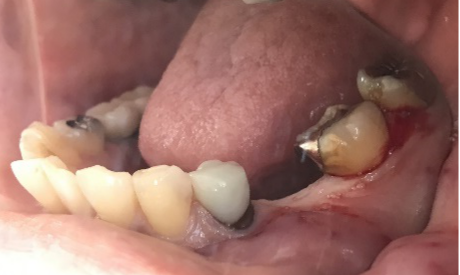

治療内容

ブリッジの支台になっている前方の歯が、歯根の破折を起こしていました。真っ二つに割れていましたので、保存することができず抜歯しました。抜歯後2本欠損のところに、2本インプラントを埋入しました。

【抜歯後】

After